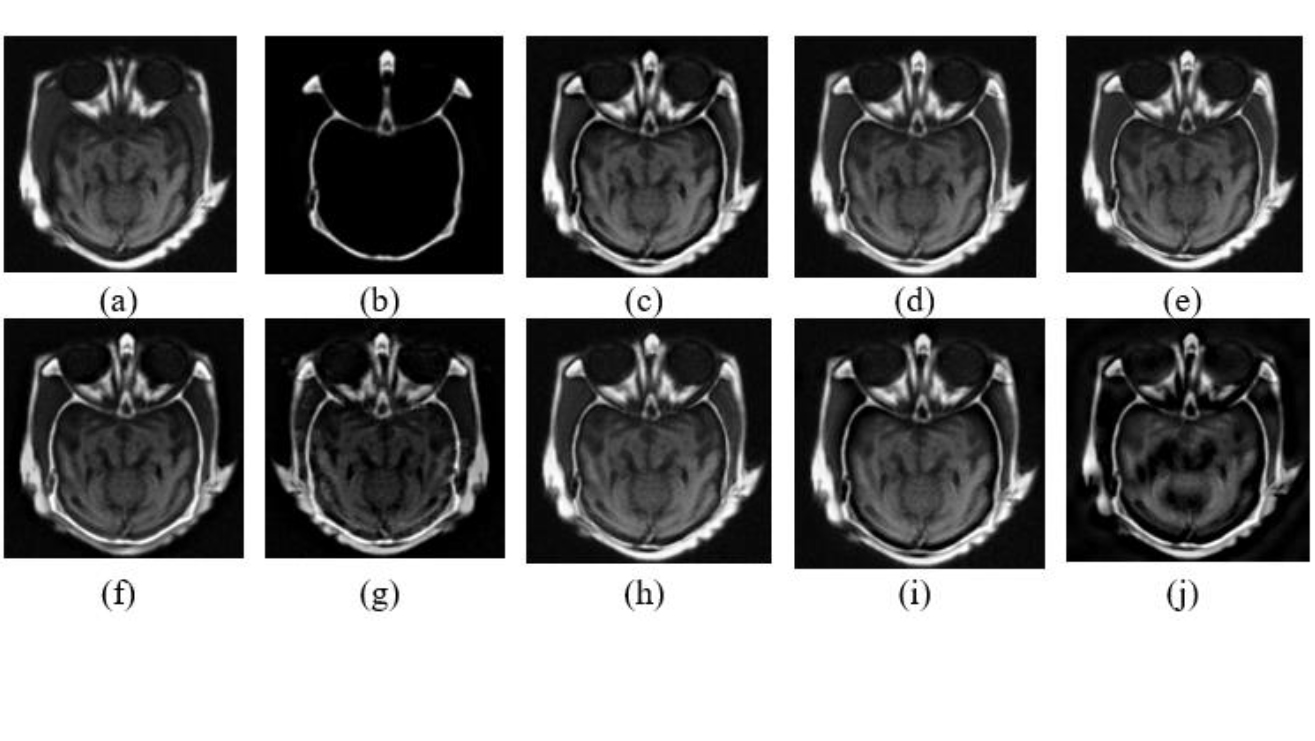

Basic methodology of CT and MRI fusion in the transform domain described along with CT and MRI images from AANLIB [19].